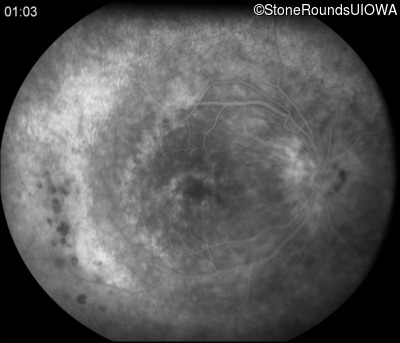

Fluorescein Angiography - Right - 20/40 -2

Exemplar